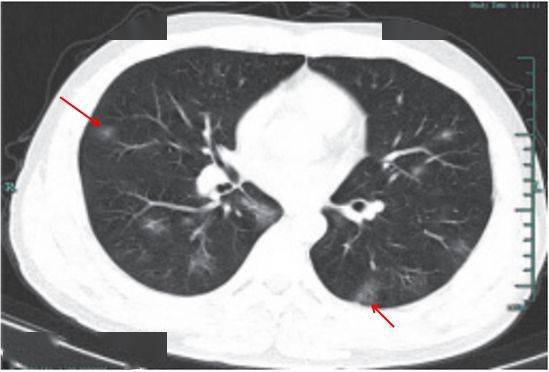

(一)病灶分布

病灶以 肺外围背侧为主,以两肺下叶为著,与胸膜常紧贴,提示新冠肺炎病变多首先侵犯皮层肺组织的细支气管及肺泡上皮, 病灶分布逐步从外周向中央扩展(图 2-1)

图2-1 早期病灶多数分布贴近胸膜( 共4张 )